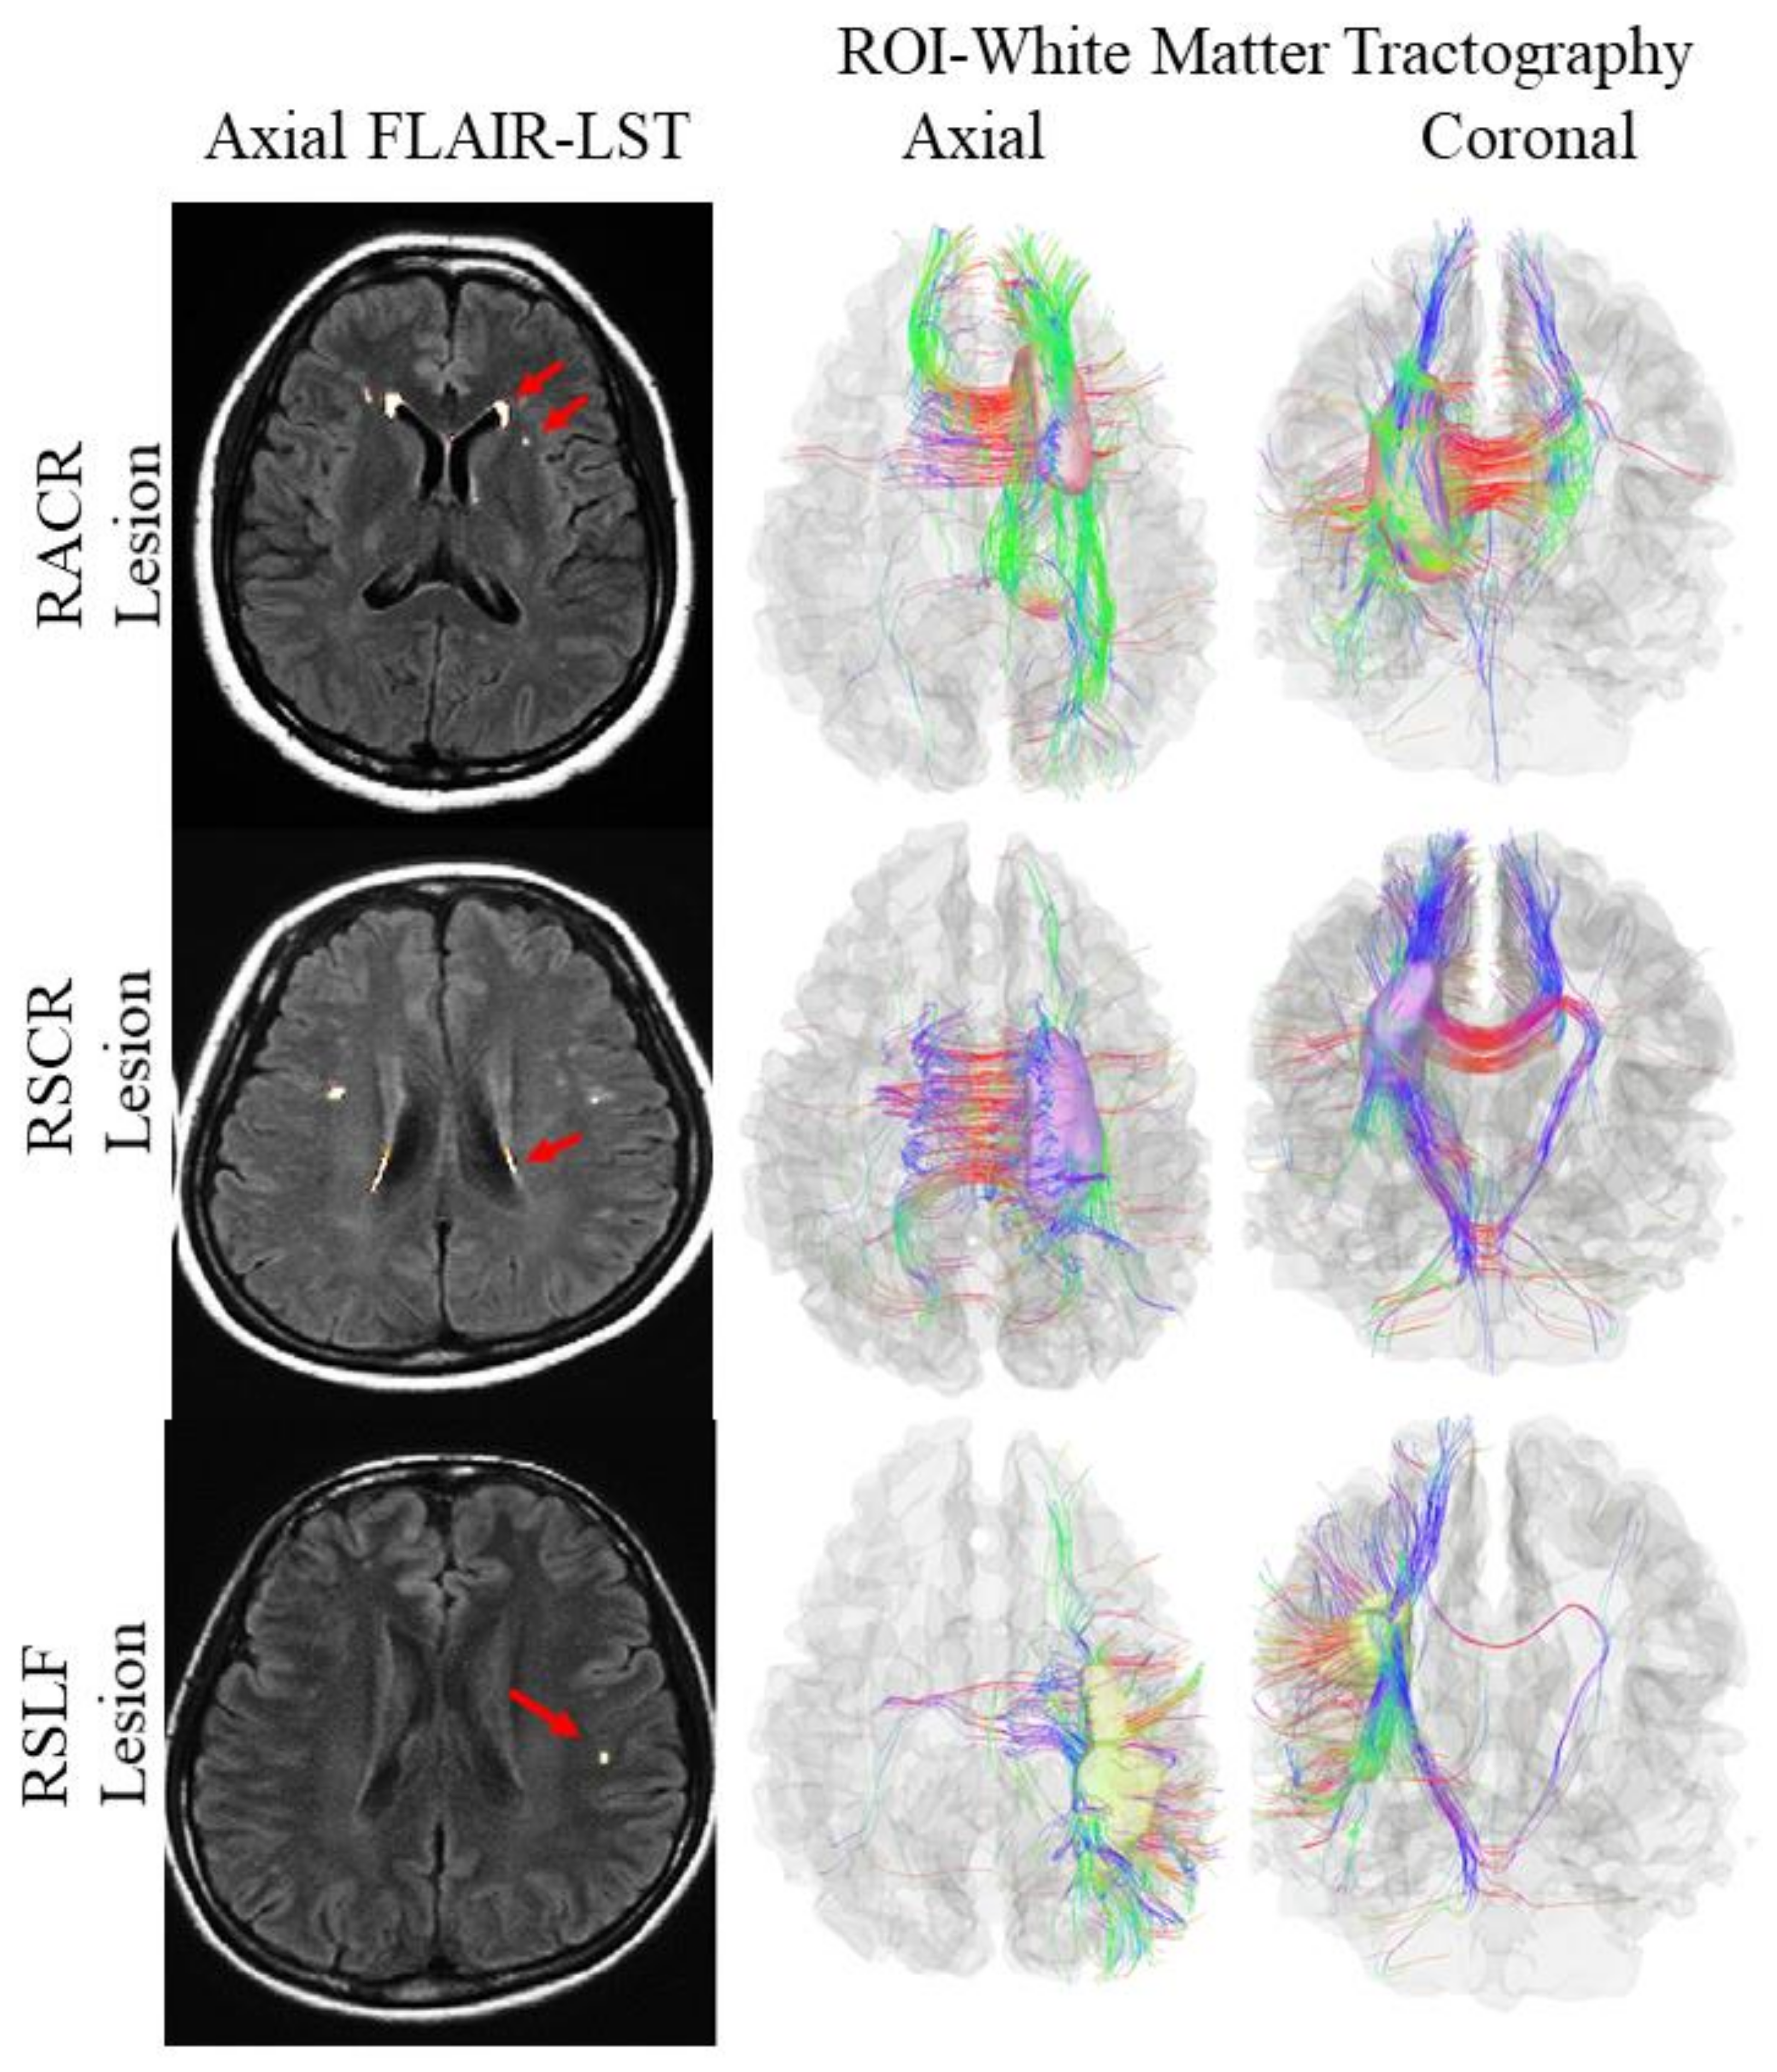

3.6. Multimodal Study for Cerebral White Matter Integrity among the Study Subjects